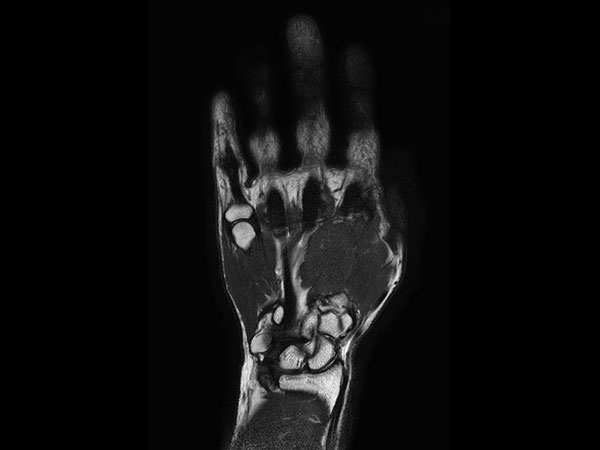

Axial T2w TSE